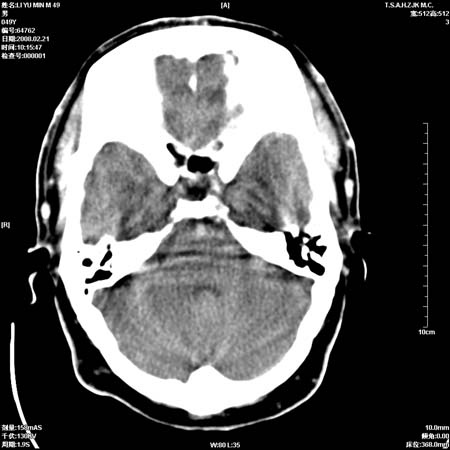

一周后复查ct:

可能为正常。间隔一周蛛血应基本吸收;再过一周复还是这样应该可以肯定了。

一周时间密度未见改变,考虑为正常图像(脑动脉硬化?)。